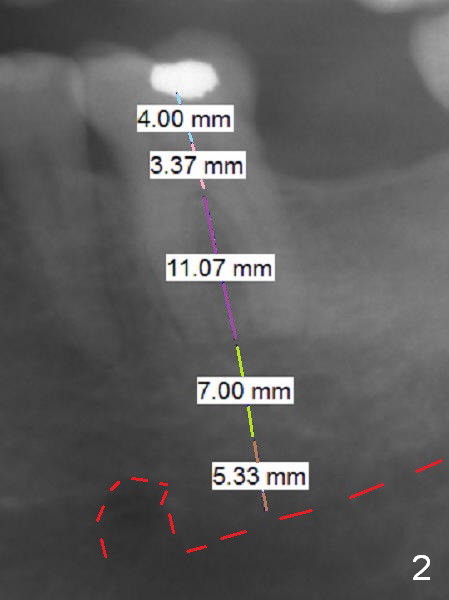

A 59-year-old man has cold sensitivity after chipping the distobuccal cusp of the tooth #19 (Fig.1 (panoramic X-ray taken 5 years ago). He is debating whether to save the tooth or not. If he chooses extraction and implant, the latter can be 18 mm (bone-level (11 (septum, purple in color)+7 (apical, green) mm), Fig.2). If the implant perforates the septum, it will achieve primary stability in the apical bone (the first of 3 fixation points). There is ~5 mm clearance (brown) from the Inferior Alveolar Canal (red dashed line). The cuff of the restorative abutment will be most likely 3 mm (pink), while the abutment is estimated to be 4 mm long (blue). After extraction (Fig.3, no Antibiotic), osteotomy will be initiated through the septum (Fig.4, 6B: red). When an implant is inserted, it may perforate the septum (Fig.5, 6C: green) into the mesial (Fig.6A: M) and distal (D) sockets. The remaining buccal (Fig.6C: B) and lingual (L) septal struts (the rest of two fixation points) contribute to implant stability.